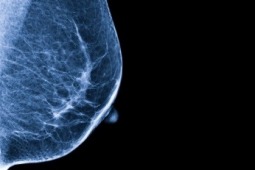

Nowe wytyczne ASCO leczenia zaawansowanego HER2-ujemnego raka piersi

2 września w Journal of Clinical Oncology opublikowano nowe wytyczne ASCO (ang. American Society of Clinical Oncology) pomagające w wyborze optymalnej terapii dla chorych na HR2-ujemnego raka piersi